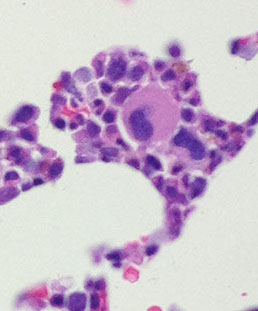

Low power morphologic abnormalities in MDS

Dys-ERYTHRO-poiesis = multinuclear, budding, megaloblastic, karyorhectic nuclei; PAS(+)/vacuoled cytoplasm

BM findings

Usually hypercellular marrow for age with erythroid hyperplasia, but may see normocellular or hypocellular marrow

Generally increased number of blasts

Generally trilineage dysplasia (dyshematopoiesis)

- Abnormal localization of immature myeloid precursors (ALIP)

Dyserythropoiesis

Erythroid dysplasia [3].